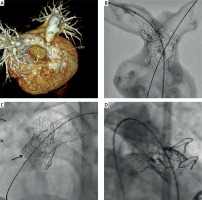

The case concerns a 17-year-old, 69 kg, asymptomatic boy after a TOF complete repair with a transannular patch. The patient was re-operated at the age of 10 with a stentless valve and only 1 year later with a 23 mm Carpentier-Edwards Perimount Magna bioprosthetic valve (Edwards Lifesciences Inc., Irvine, USA). Pulmonary stenosis (PS) with maximum/mean gradient of 100/55 mm Hg, moderate pulmonary regurgitation, and dilated right ventricle were established during transthoracic echocardiography. Computed tomography (CT) revealed a 12 mm supravalvular PS and proximal narrowing of pulmonary arteries: right (RPA) to 9 and left (LPA) to 6 mm (Figure 1 A).

Figure 1

A – Computed tomography of a 17-year-old tetralogy of Fallot patient after bioprosthetic Edwards Magna valve (BPV) surgical replacement. Supravalvular pulmonary (PS) and bifurcation stenosis. B – Three-dimensional computed tomography-derived silicone model of the right ventricle outflow tract with supravalvular (PS) and bifurcation stenosis: 48 mm AndraStent XXL implanted into PS and LPA and through this stent’s cells a 21 mm AndraStent XXL was implanted in the RPA. C – 48 mm AndraStent XXL implanted into both PS and LPA and 21 mm AndraStent XXL implanted into RPA. Lower frame of 23 mm Magna valve cracked at 18 atm with 24 mm Atlas balloon, arrow – frame separation. D – 23 mm Edwards Sapien XT valve implanted in the upper part of a 23 mm Magna valve

RPA – right pulmonary artery, LPA – left pulmonary artery.

In order to test transcatheter treatment options, a 3D CT-derived silicone model of the aforementioned region with an embedded valve was prepared. Subsequently, the Y-stenting technique for bifurcation stenosis was selected. This includes implantation of a long hybrid-cell designed stent into the supravalvular PS and LPA and another stent into the RPA through the struts of the first stent (Figure 1 B). Moreover, an experimental bench test with cracking of the 23 mm Magna BPV using a 24 mm Atlas balloon (Bard Peripheral Vascular Inc., Tempe, USA) was performed. The lower restrictive frame of the valve cracked at 14 atm. A preprocedural CT scan excluded risk of coronary artery compression in the intended valve landing zone. Finally, the patient was qualified for ViV TPVR and informed consent was obtained.